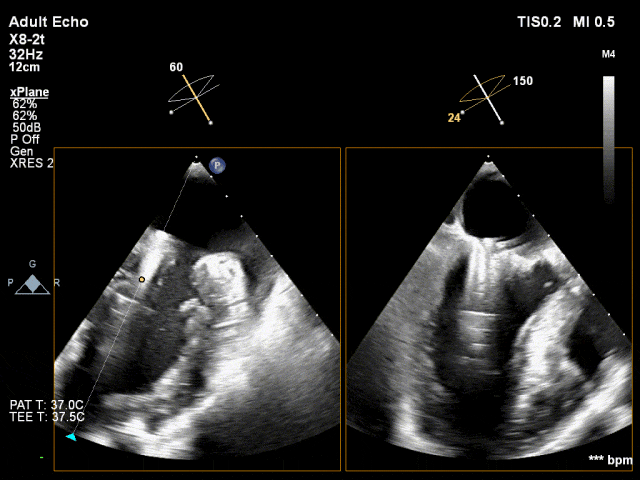

全麻后,首先在心前区的肋间切开3-4CM小切口,暴露心脏的心尖位置,心尖穿刺后进入导丝,利用导丝交换导管鞘完成通路建立。将系统送入左心房,顺利到达二尖瓣病变区域。在经食道超声引导下,术者通过反复评估二尖瓣反流位置、抓捕位置、反流程度,在2区主动脉瓣与二尖瓣闭合线垂直进行巧妙夹合,最终植入一枚ValveClamp®MVC-Ⅲf夹。超声评估夹子固定良好,组织桥完整,无葫芦征,位置、轴向均符合预期。患者术后反流程度从大量转至少量,手术取得圆满成功。患者恢复良好,已经顺利出院。

捕获瓣叶,进行夹合 3D切面调整位置及钟向

反流得到明显改善 术后3D动图